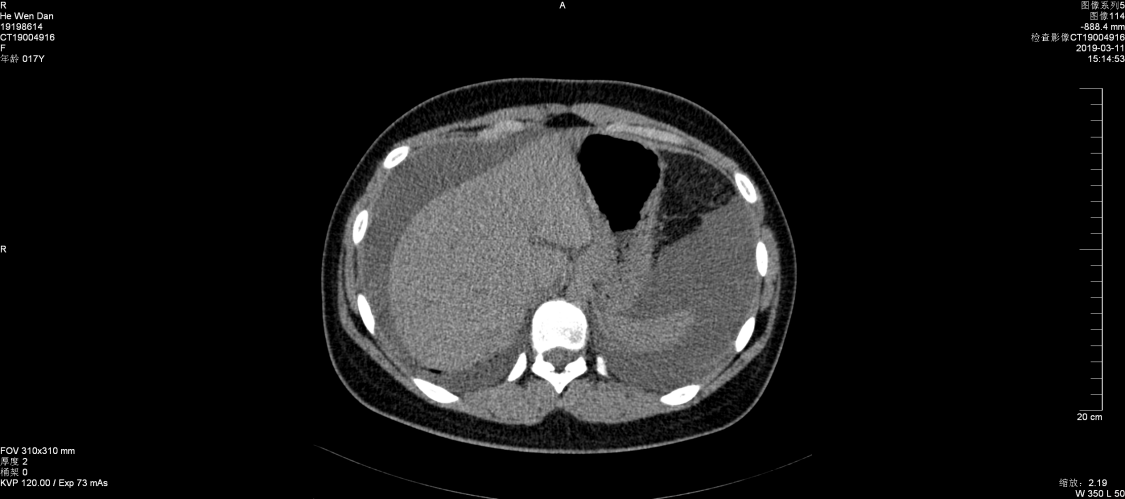

2019年3月11日,消化内科收治一名女性患者,16岁,以“腹胀1周、腹泻、腹痛1天”之主诉入院,查体:生命体征平稳,皮肤未见皮疹,心肺未见异常,腹部有柔韧感,无明显压痛,移动性浊音阳性。B超提示盆腔、腹腔积液,门诊按“急性胃肠炎”收治。入院后检查结果,血常规:白细胞22.52×109/L,嗜酸细胞比率21.2%,最高达48.6%。嗜酸细胞计数:10.81×109/L,B超提示腹膜增厚,伴大量腹水。胃镜检查:胃窦部粘膜充血、水肿,幽门狭窄,疑幽门梗阻,胃镜活检可见大量嗜酸细胞浸润。

张永红主任查房考虑为嗜酸粒细胞性胃肠炎,组织全科讨论,结合临床表现及检查结果,并排除引起嗜酸性粒细胞增多的疾病,最后诊断为:嗜酸粒细胞性胃肠炎。果断给予强的松30mg一次/日,三天后症状减轻,腹水减少,复查血常规、腹部B超较前好转,一周后患者腹水消失,症状消失,除嗜酸细胞值高以外,血常规正常,痊愈出院。建议病人定期门诊复查,目前激素仍在减量之中......